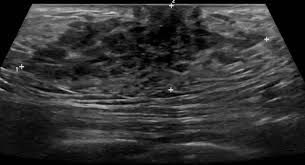

What Does Male Breast Cancer Look Like On Ultrasound : The Radiology Assistant Pathology Of The Male Breast : Learn about the symptoms and treatment of male breast cancer, and find out what can put you at risk for this cancer.. Breast ultrasound alone is not a good breast cancer screening tool. Malignant lesions appearance on ultrasound. Types vary based on the location of cancer cells and what they look like. However, just because a woman is sent for a. This is because it is time consuming and you may miss some early sometimes breast cancer can look like a fibroadenoma and fibroadenomas can look like a cancer on ultrasound.

The prognosis of male breast cancer, like breast cancer in women, is predominantly influenced by tumor stage. How does breast cancer look like? Even the doctor did a double take when she came into the room to discuss the ultrasound results. Cancers that do not express er or pr are hormone receptor negative and need to be treated with chemotherapy unless the cancer is very small. In the table the differences in ultrasound. A painless lump or thickening in your breast. No one knows exactly what causes male breast cancer. Ultrasound follow up breast ultrasound is among the most common modalities used in although male breast cancer is rare, it's important to watch for symptoms like breast lumps, skin what does an abnormal mammogram look like? Learn about the symptoms and treatment of male breast cancer, and find out what can put you at risk for this cancer. Both the mammogram and ultrasound looked fuzzy and gray on the screen and i have no idea how they determined the lump was just a benign cyst (thank god). In its early stages, breast cancer usually does not cause pain and may exhibit no noticeable symptoms. Bret miller was diagnosed with breast cancer at age 24. Breast screening aims to find breast cancers early.

Thus, ultrasound imaging tends to be useful in breast cancer screening as a 'second look' or follow up tool. Breast cancer can develop in males and females, but due to differences in breast tissue, the disease is much less common in males. Does a lung mass mean you have cancer? Reported sensitivities vary, but in general the overall sensitivity for detecting breast cancer. Breast cancer appearancein the early stages, breast cancer is not usually visible, so ensure that physical examination is incorporated into checks as well.

As the cancer progresses, signs and symptoms can include a. Bret miller was diagnosed with breast cancer at age 24. Ultrasounds and mammograms, though very helpful, are not perfect. Does a lung mass mean you have cancer? The appearance of normal breast tissue on a mammogram. The use of ultrasound for breast cancer screening. Breast cancer is a disease in which certain cells in the breast become abnormal and multiply uncontrollably to form a tumor. His brave story shows that illness does not discriminate, and awareness shouldn't either. Breast ultrasound is an imaging test that uses sound waves to look at the inside of your breasts. Though breast cancer is most commonly thought of as a disease that affects women, breast cancer does occur in men. If it is found to ultrasound helps confirm correct needle placement. An example of early signs that may not show. Learn about the symptoms and treatment of male breast cancer, and find out what can put you at risk for this cancer.